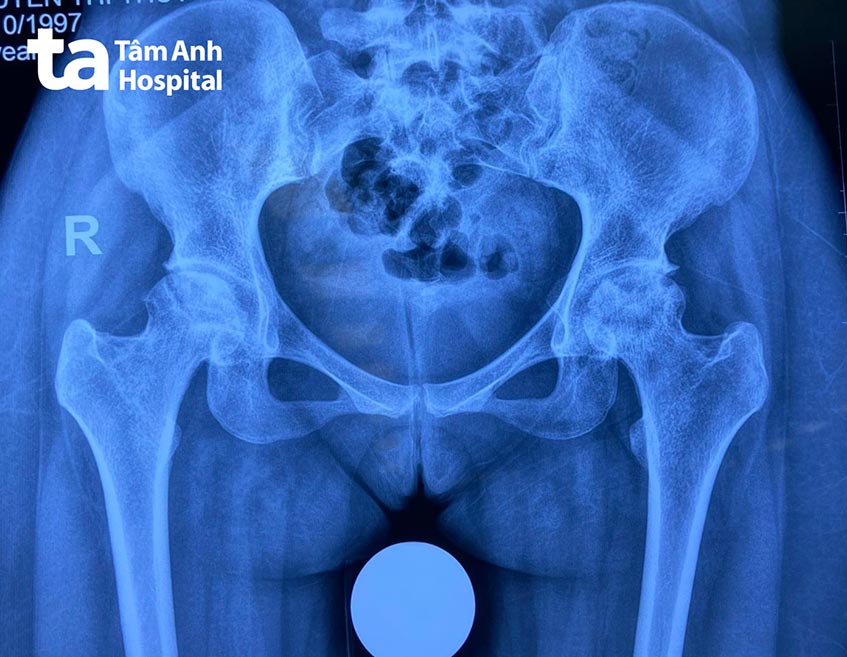

ThS.BS.CKI Lê Đình Khoa, Trưởng khoa Tái tạo khớp, cho biết người bệnh bị hoại tử chỏm xương đùi ở cả hai bên khớp háng. Đây là bệnh lý có thể được điều trị bảo tồn bằng cách dùng thuốc và tập vật lý trị liệu. Tuy nhiên, khi bệnh đã tiến triển nặng, gây đau đớn dữ dội và ảnh hưởng nghiêm trọng đến sinh hoạt hàng ngày như trường hợp của chị Thúy, người bệnh được chỉ định thay khớp háng bằng phương pháp SuperPath.

Bác sĩ Khoa cho biết hoại tử chỏm xương đùi là tình trạng vùng chỏm xương của người bệnh thưa dần, hình thành những nang xương; lâu dần gây gãy xương dưới sụn, xẹp chỏm xương đùi, mất chức năng khớp háng. Bệnh lý này có thể xảy ra do chấn thương, xuất hiện cục máu đông, sử dụng corticoid trong thời gian dài, lạm dụng rượu bia,… Nếu không được điều trị kịp thời, người bệnh có nguy cơ tàn phế rất cao.